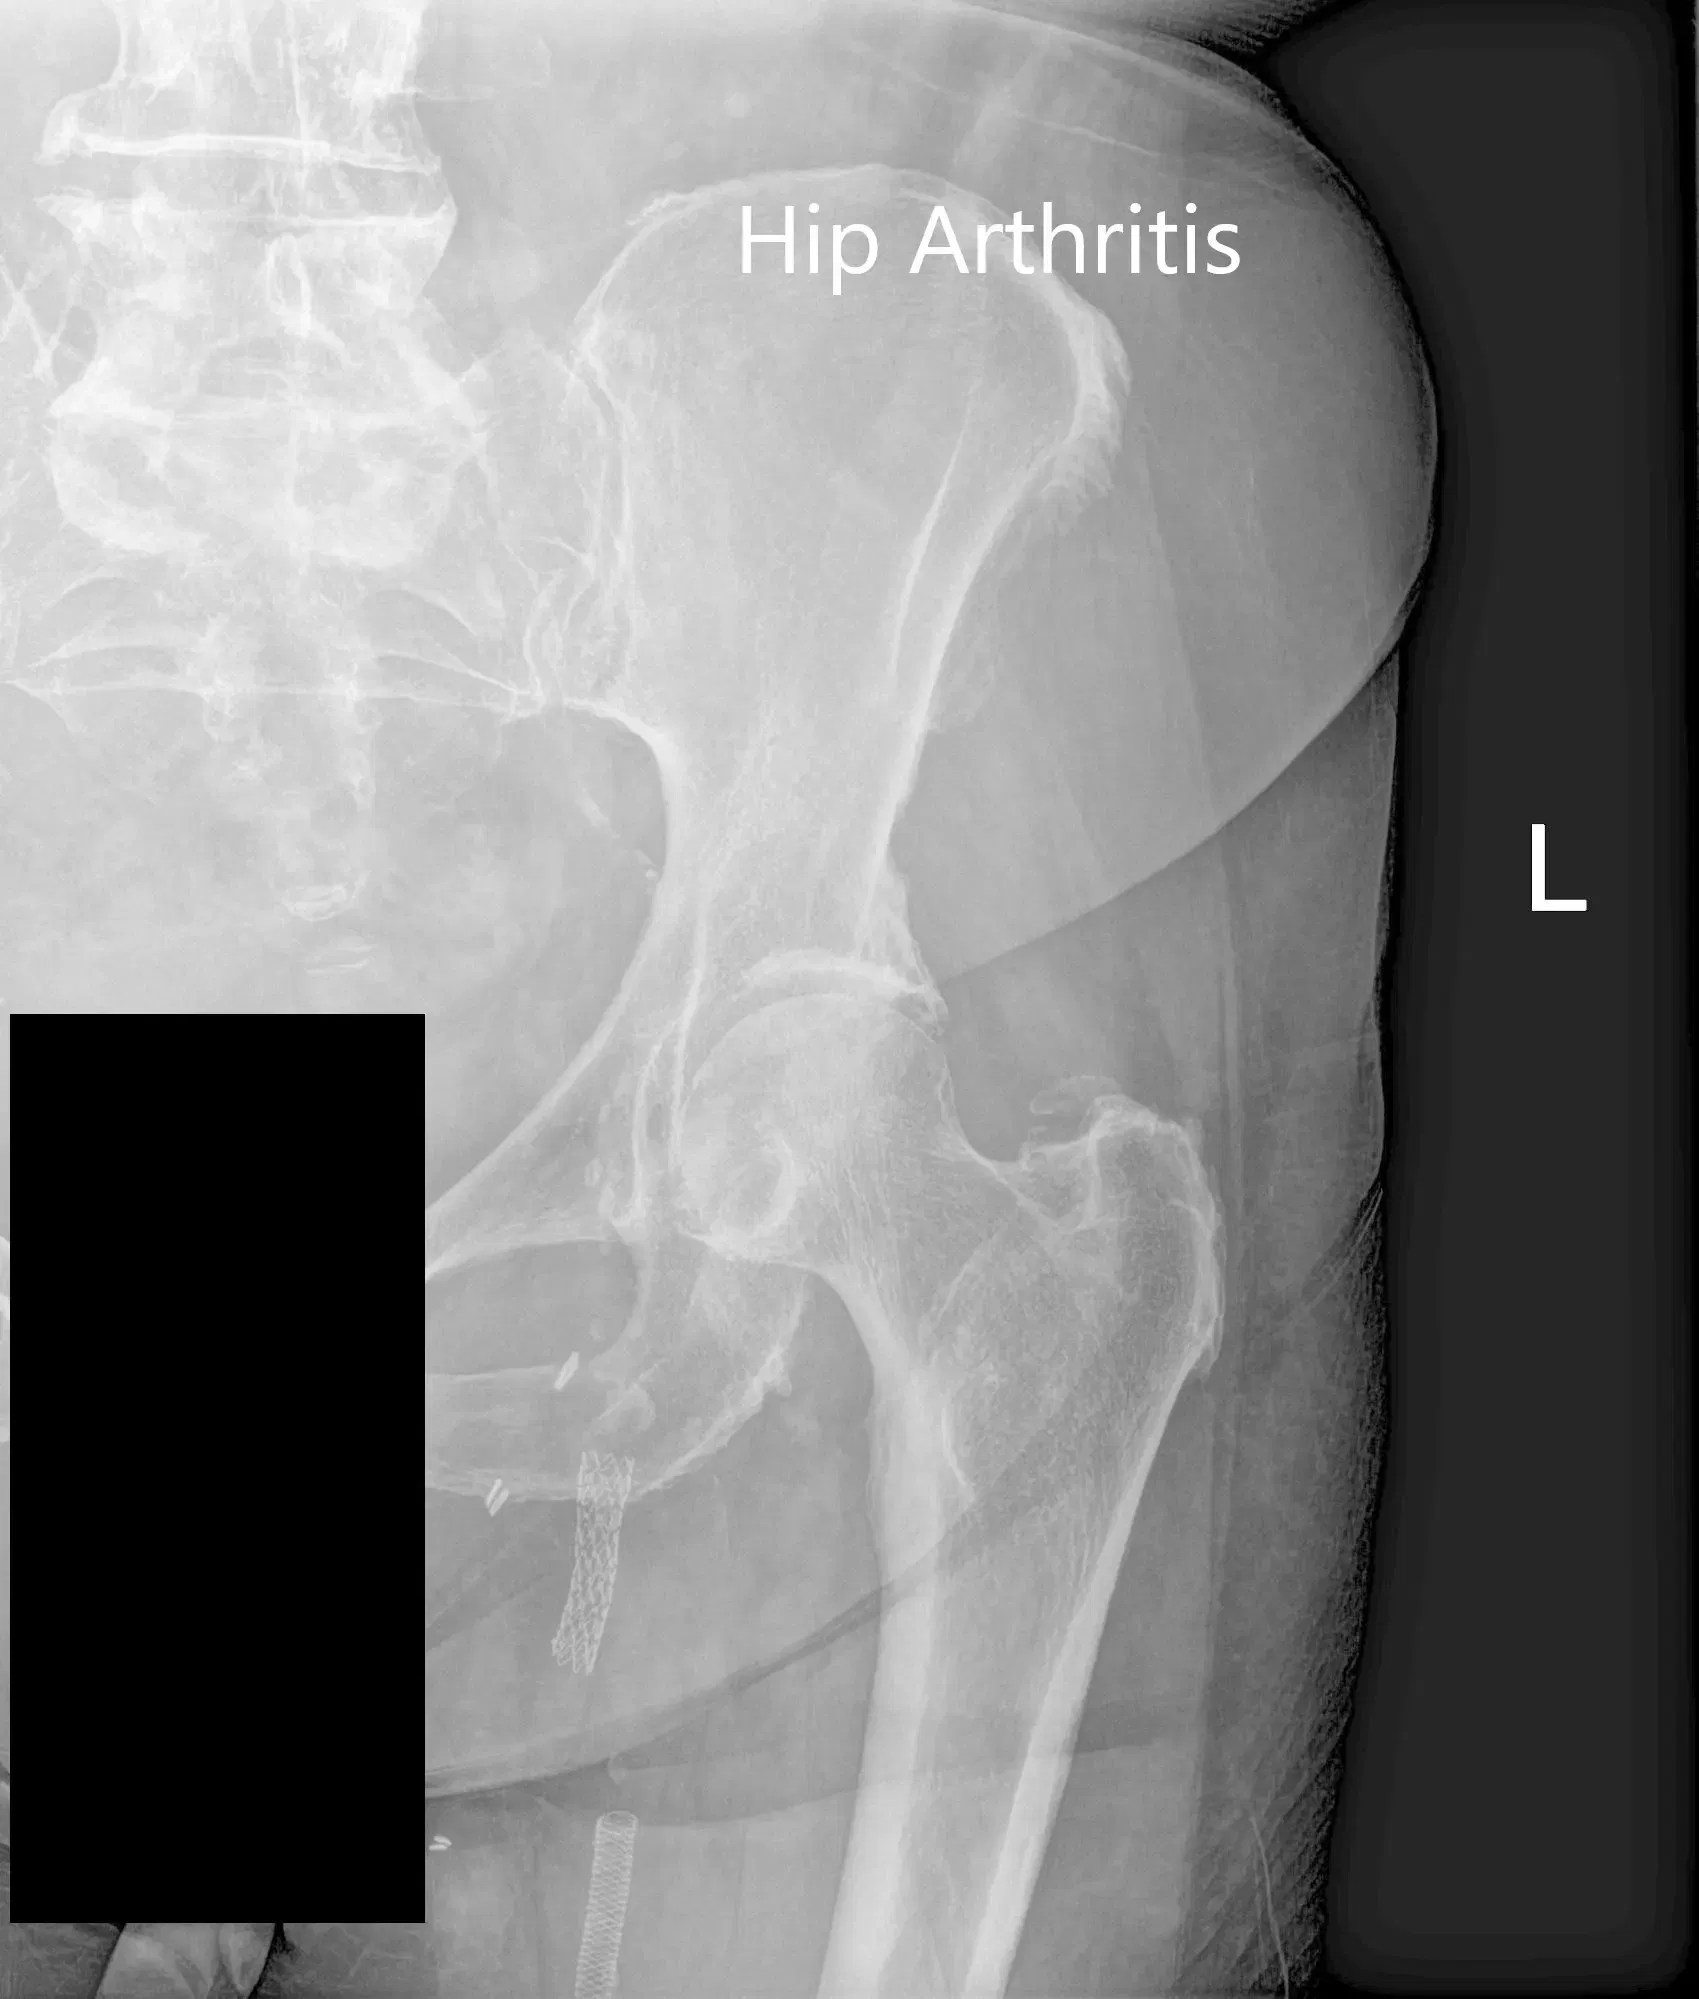

Imaging study revealed bilateral arthritis of the hip joint. There were severe degenerative changes on the left hip. After careful consideration of his cardiac risk factors, he was advised left total hip arthroplasty. Risks, benefits, and alternatives were discussed with him at length. He agreed to undergo left hip replacement.

Preoperative X-ray of the left hip showing AP and frog-leg lateral views